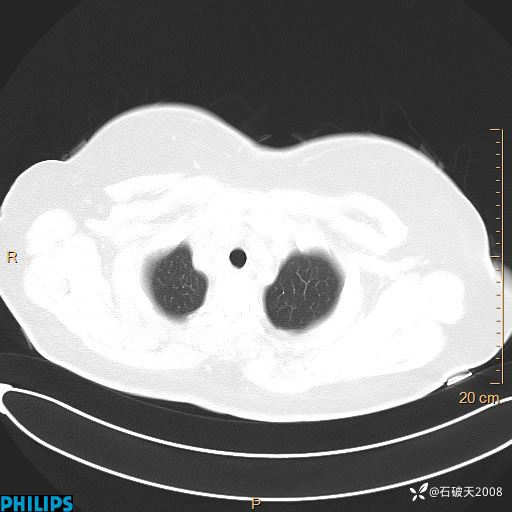

肺结节病?纵膈型肺癌?淋巴瘤?有点意思,欢迎围观

女 52岁 主 诉:咳嗽10余天,咳痰2天。

现病史:10余天前无明显诱因出现咳嗽,呈阵发性干咳,伴咽喉部发痒,无咽痛,无咳痰,无鼻塞、流涕、打喷嚏,无发热、畏寒、寒颤,无头痛、头晕,无胸闷、胸痛,无反酸、烧心,无腹痛、腹泻,无尿频、尿急,无皮疹等,在当地诊所求治,给予口服药物治疗(具体不详),病情无好转。遂在当地社区卫生服务中心开具口服药物治疗(具体不详),疗效欠佳。2天前出现咳痰,在我院门诊求治,行胸部CT提示肺部感染,建议住院,患者要求口服药物治疗,目前仍咳嗽、咳白色粘痰,白天量多,夜间自觉喉部喘鸣音,遂再次来院就诊,以“肺部感染”为诊断收入院。发病以来,神志清,精神可,饮食可,夜间睡眠差,大小便正常,近期体重无明显变化。

肺窗